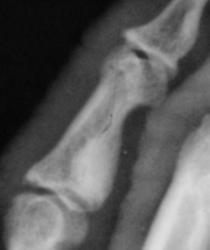

Катенёв Валенти... Дата публикации 19.06.2009, 20:43 Ваше мнение коллеги по поводу локального "уплотнения костной ткани" в средней фаланге 5 пальца левой кисти. Эностоз? Ваше мнение коллеги? Пт, 19/06/2009 - 20:46 #1 Глазков Игорь А... Не на сайте Был на сайте: 11 месяцев 3 недели назад Зарегистрирован: 19.12.2008 - 20:41 Публикации: 1597 что эностоз, но неплохо бы узнать возраст пациента. Прийди к Себе Пт, 19/06/2009 - 20:52 #2 Катенёв Валенти... Не на сайте Был на сайте: 7 лет 3 месяцев назад Зарегистрирован: 22.03.2008 - 22:15 Публикации: 54876 Пациент возраста около 30-ти лет.

Пациент возраста около 30-ти лет.